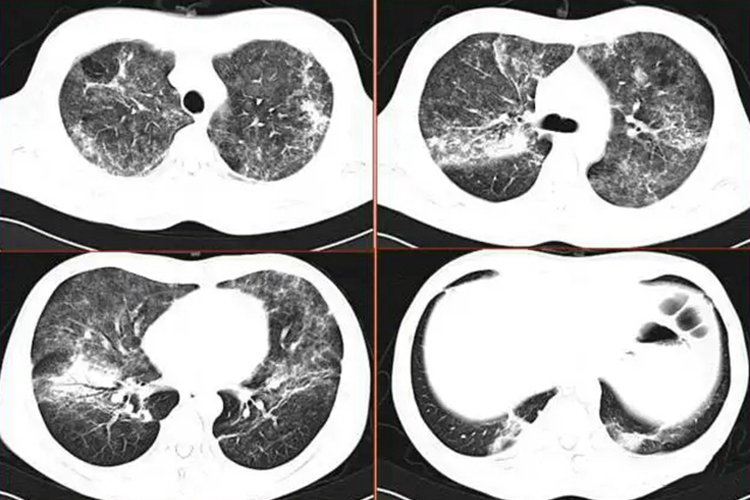

CT表现为肺部结节,结节多为孤立性,亦可为多发结节,结节大小不等,形态不规则,但绝大多数位于肺外带及胸膜下,可有边缘光滑的空洞形成并累及胸膜。偶尔呈弥漫性粟粒影,少数为局限性浸润性实变。